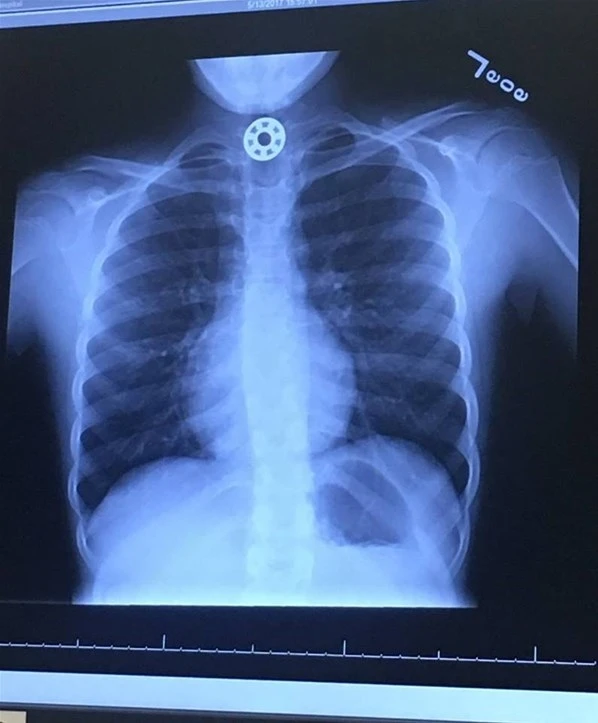

Houston'ın hemen kuzeyinde, The Woodlands'daki Texas Çocuk Hastanesine götürülen çocuğun yutağında bilye büyüklüğünde bir şeyin sıkıştığı görüldü ve hemen ameliyat yapılması gerektiği söylendi.